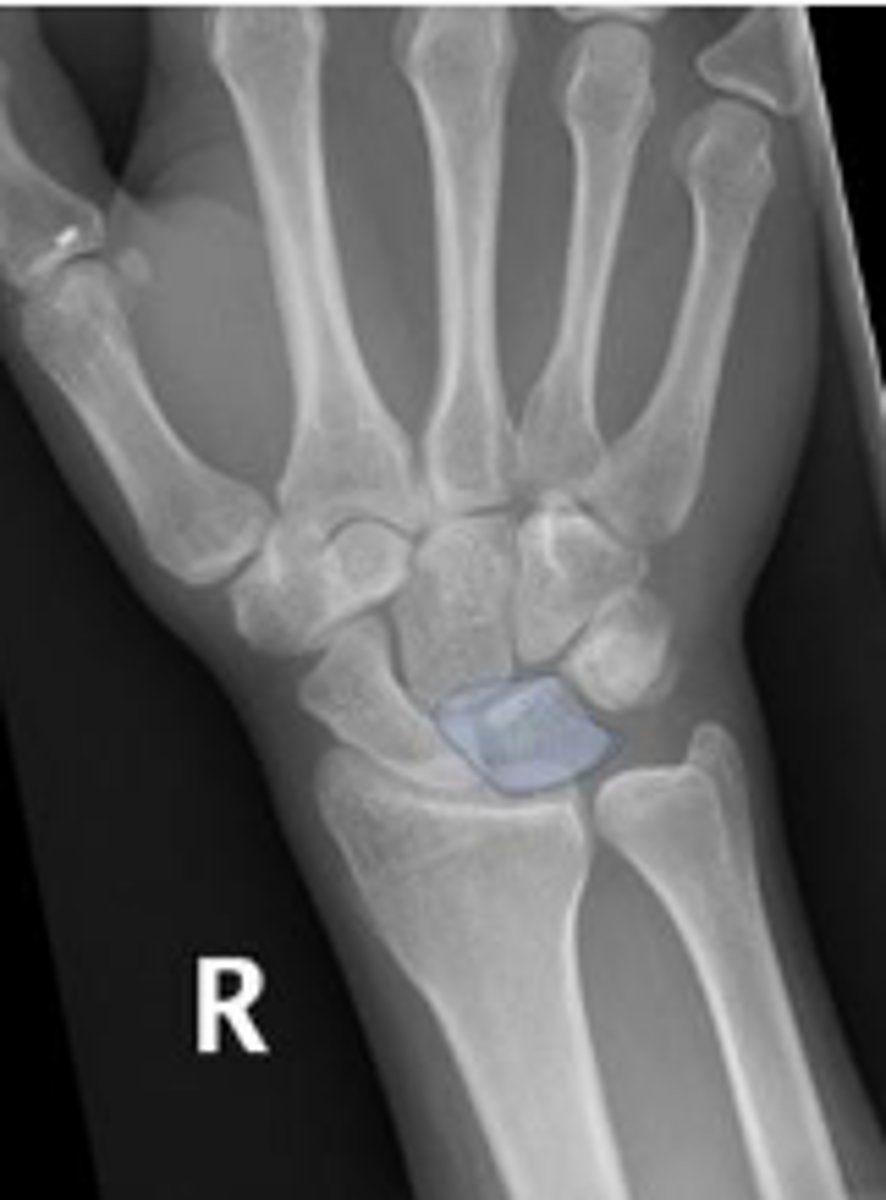

PA right wrist

Right scaphoid

What is outlined?

What is the arrow pointing to?

3 arcs of carpal alignment

What is the name of the assessment

Proximal cortical aspect of the first (proximal)

carpal row (ARC 1)

What are the landmarks for the most proximal line in the assessment?

Distal cortical aspect of the first (proximal) carpal

row (ARC 2)

What are the landmarks for the most middle line in the assessment?

Proximal cortical aspect of the second (distal)

carpal row (ARC 3)

What are the landmarks for the most distal line in the assessment?

SLAC wrist; carpal dislocation, carpal fracture

Name 2 conditions that will result in an alteration of the assessment?